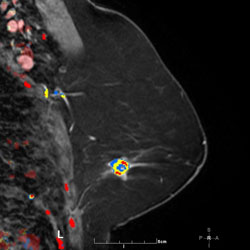

Palpable mass in the upper breast

Palpable mass in the upper breast shown on mammography to be irregular.

MR MIP image

MR MIP image again shows the irregular mass in the upper outer breast. Histology revealed a T2, N0, M0 invasive ductal carcinoma (ER/PR +, Her-2 neu -) and high-grade ductal carcinoma in situ.